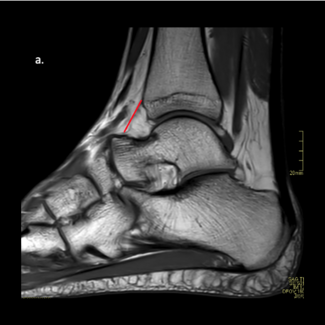

A. Douglas Spitalny, DPM, FACFAS

My focus is simple: I want to highlight commonly missed MRI pathology. This educates not just our patients but ourselves on the benefits of surgery.